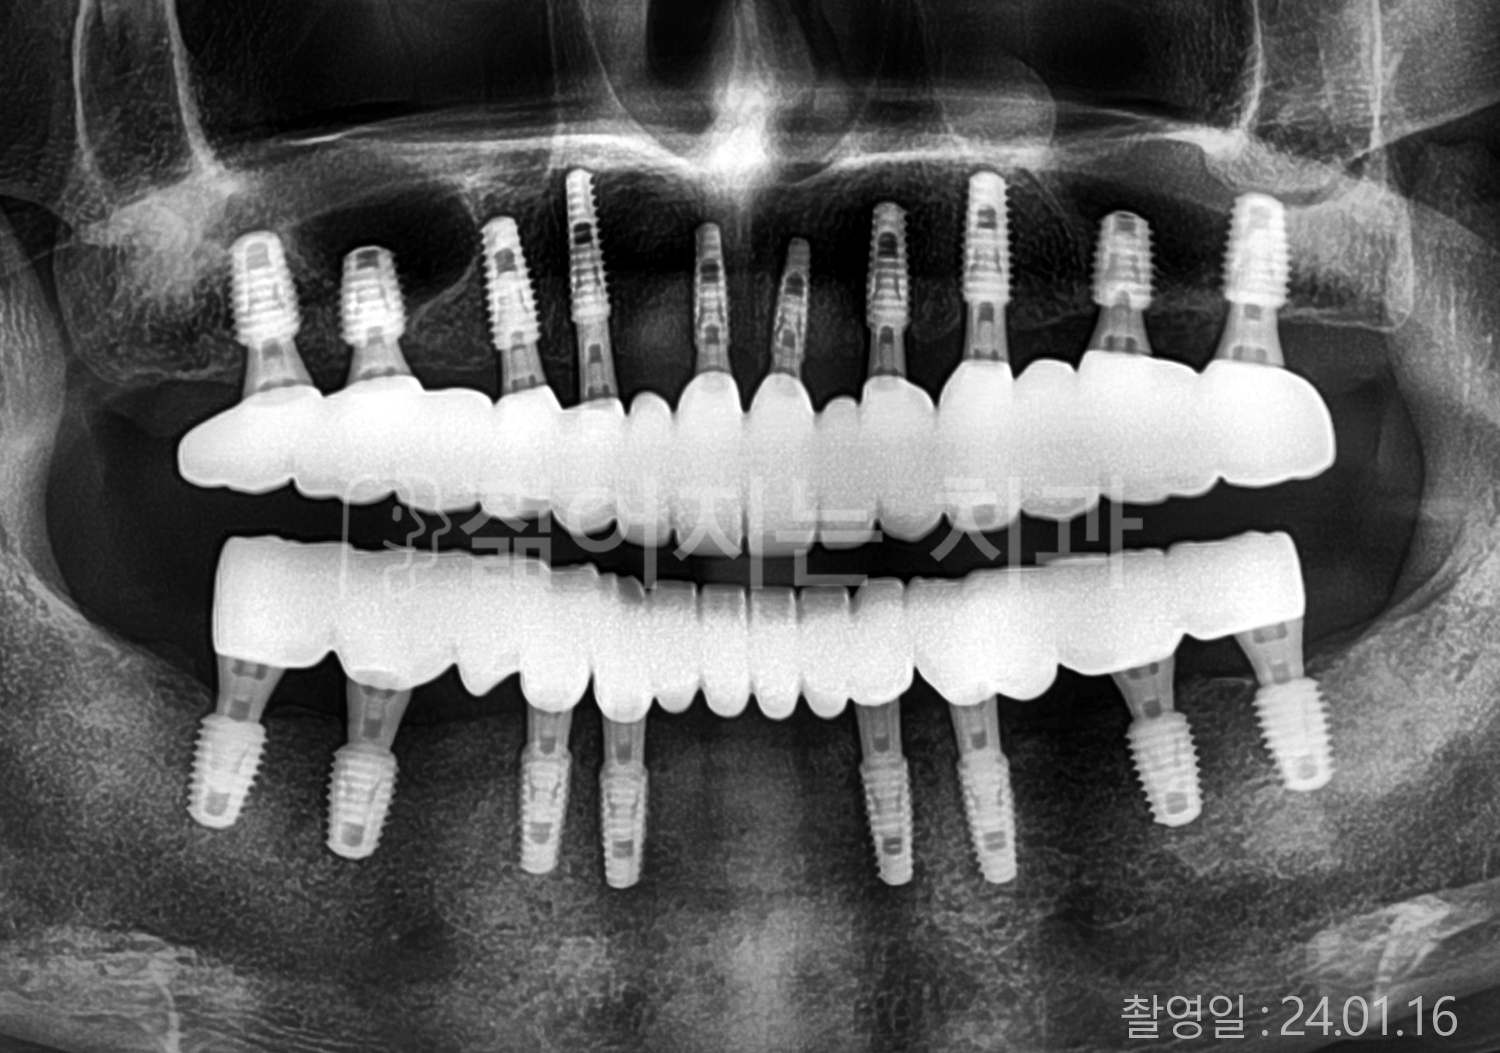

• 70대 고혈압, 당뇨 전체치아 10개 이상 임플란트

• 50대 고혈압, 당뇨 전체치아 10개 이상 임플란트

• 60대 고혈압, 당뇨 전체치아 10개 이상 임플란트

• 50대 전체치아 10개 이상 임플란트

• 70대 당뇨 전체치아 10개 이상 임플란트

• 80대 전체치아 10개 이상 임플란트

• 40대 전체치아 10개 이상 임플란트

• 60대 고협압, 고지혈증 전체치아 10개 이상 임플란트

• 60대 전체치아 10개 이상 임플란트